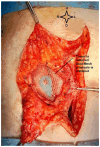

Cervical cancer is the fourth most common cancer in women, the highest mortality being found in low- and middle-income countries. Abdominal parietal metastases in cervical cancer are a very rare entity, with an incidence of 0.1-1.3%, and represent an unfavorable prognostic factor with the survival rate falling to 17%. Here, we present a review of cases of abdominal parietal metastasis in recent decades, including a new case of a 4.5 cm abdominal parietal metastasis at the site of the scar of the former drain tube 28 months after diagnosis of stage IIB cervical cancer (adenosquamous carcinoma), treated by external radiotherapy with concurrent chemotherapy and intracavitary brachytherapy and subsequent surgery (type B radical hysterectomy). The tumor was resected within oncological limits with the histopathological result of adenosquamous carcinoma. The case study highlights the importance of early detection and appropriate treatment of metastases in patients with cervical cancer. The discussion explores the potential pathways for parietal metastasis and the impact of incomplete surgical procedures on the development of metastases. The conclusion emphasizes the poor prognosis associated with this type of metastasis in cervical cancer patients and the potential benefits of surgical resection associated with systemic therapy in improving survival rates.